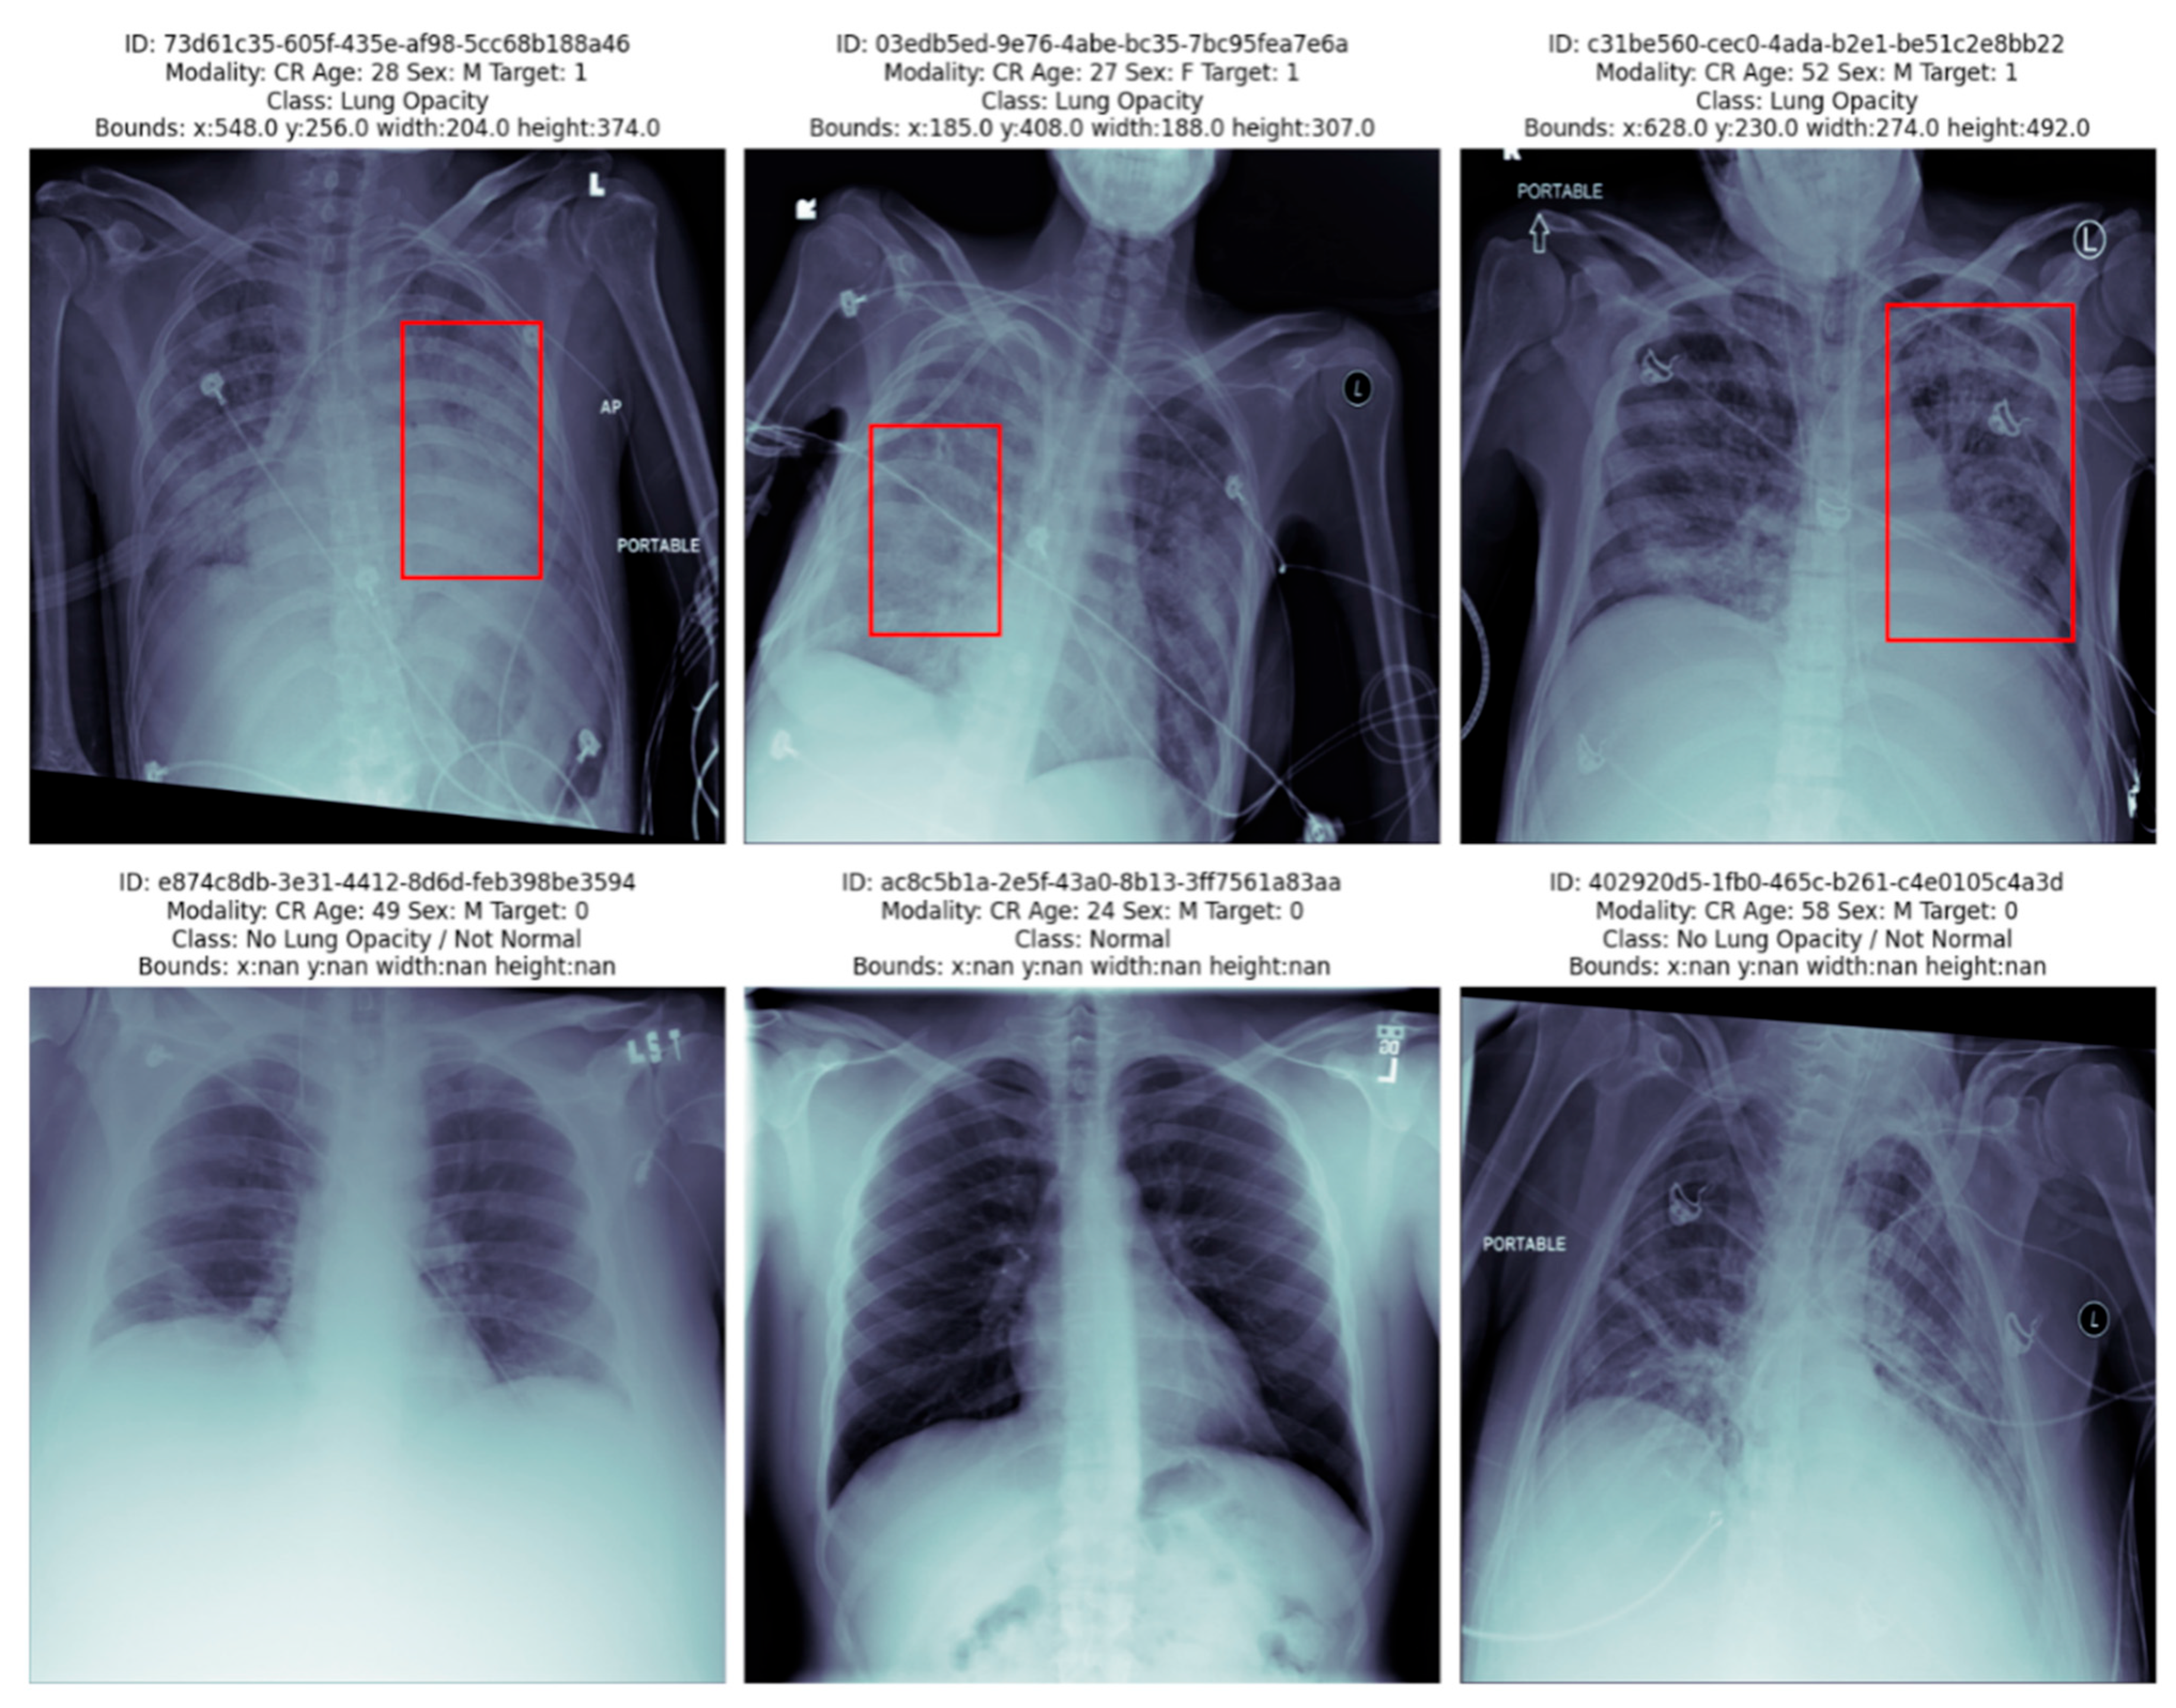

- No Lung Opacity/Not Normal: no lung abnormalities detected;

- Normal: abnormalities unrelated to pneumonia;

- Lung Opacity: opacities that are visible, indicating pneumonia presence.

- Pneumonia (1): from Lung Opacity category;

- Non-Pneumonia (0): from No Lung Opacity and Not Normal and Normal categories.

3.8. Qualitative Evaluation of CNN and ResNet50 Models